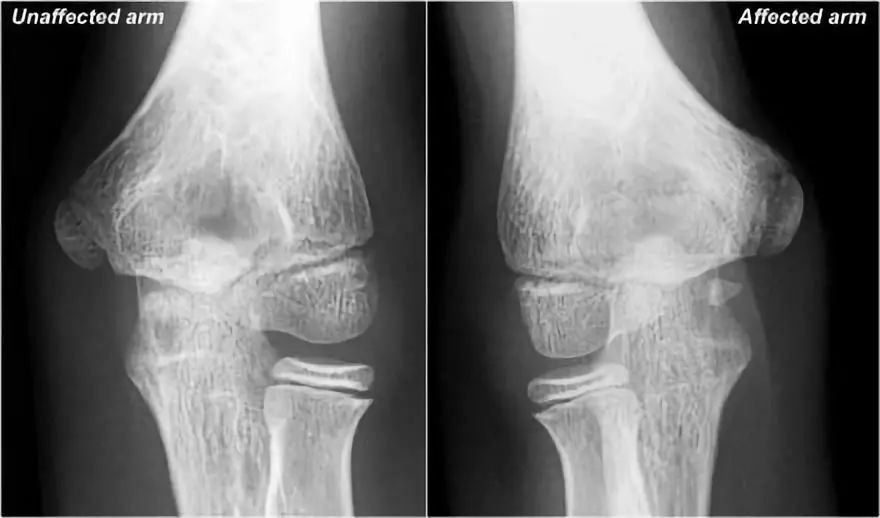

小联盟球员的手肘(Little Leaguer’s Elbow):患臂内上髁骨质减少。

在这些情况下,我们通常会要图像求比,因为它可能非常细微。诊断是Little leaguer的肘部是由慢性压力损伤引起的。在X射线照片,它看起来像一加宽的骨骺线,是由于在干骺端软骨向内生长。

● 在MR上,异常非常明显。内侧上髁和相邻骨中存在骨髓水肿(黄色箭头)。● Little Leaguer的肘部也被称为内侧性上睑下垂,有些人称之为骨骺溶解。● 顺便说一下,如果是急性创伤事件,这也可以称为Salter-Harris I型骨折。● 注意正常的尺侧副韧带(红色箭头)。在儿童中,外翻应力的薄弱环节不是尺侧副韧带,而是骨骺。

下面是另一种情况。这个病人年龄偏大。左上髁已经融合,但在右边,古河仍然有点开放。

在MR上有骨髓水肿。请注意,尺侧副韧带附着也有一些水肿,所以也有一些UCL的撕裂。